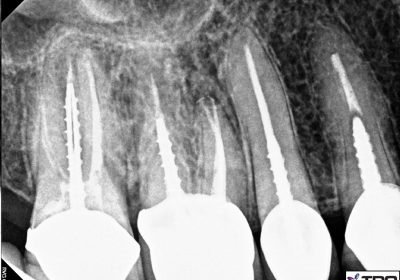

Traetment of Severe Pain with Root Canal Treatment A  aptient complains of severe pain when he calls our office.His appointment is scheduled asap. On examination it is found that he has several decayed teeth.The pain is sponteneous ,without any trigger factors like chewing or drinking and especially at night. After careful examination it is decide to start the endodontic therapy[Root Canl Treatment[ right away.The root canal is opened and cleaned and a suitable dressing is given. The aptient reports the next day with absolutely no pain.Other Root Canls are also completed as planned. Sebsequently Posts are placed and crowns are fabricated.

Dr. Ashsh Shah Dr. Ashish Shah is a qualfied Endodontist from the University of Bombay.He completed his masters in 1993.He has a rich experience of almost 30 years as of now in 2020.He is in Private Practice in Mumbai,India.He is passionately involved In the use of latest techological advancements in the field of Endodontics. 99% of the cases are done in a single visit ! The practice uses 1]Lasers 2]Rotary instruments from leading manufacturers like Micro-Mega,Dentsply Sirona 3]Pup Testers 4]Apex Locators 5]RVG etc

Pain-free Root Canal Treatment with Lasers,Disposable Rotary and Gutta Core Obturation